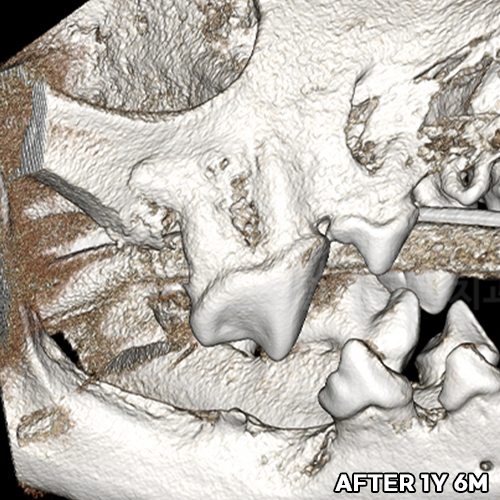

[최소침습적 발치 후 재생된 강아지 잇몸뼈]

샘플